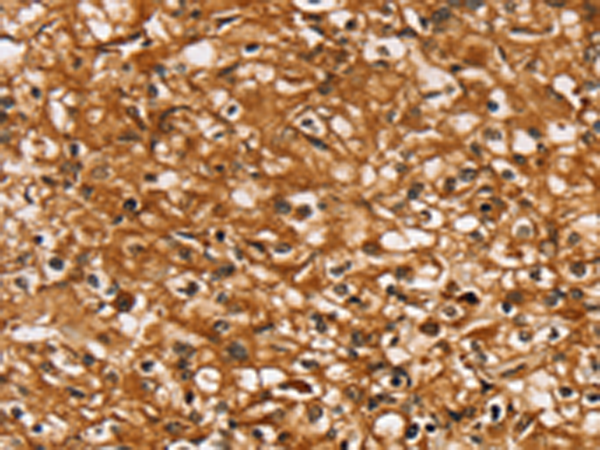

分类: 科研抗体货号: P05301别名: PHC; PTP; OK/SW-cl.48应用: IHC反应种属: Human, Mouse, Rat